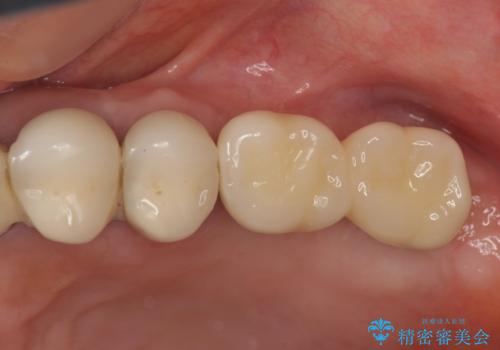

遊離端ブリッジ インプラント補綴への設計変更

- 80万円(ストローマンインプラント×2・チタンカスタムアバットメント×2・ジルコニアクラウン×2)費用は治療当時の料金となります

力学的に無理のある遊離端ブリッジをインプラントを用いて長期的な予後を見込める補綴状態へと改善しました。